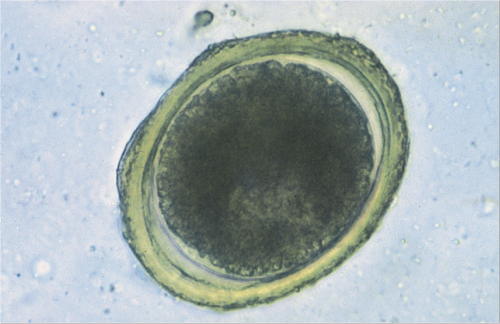

Микрофотографии яиц гельминтов Toxocara canis

Раздел: Фотоэссе